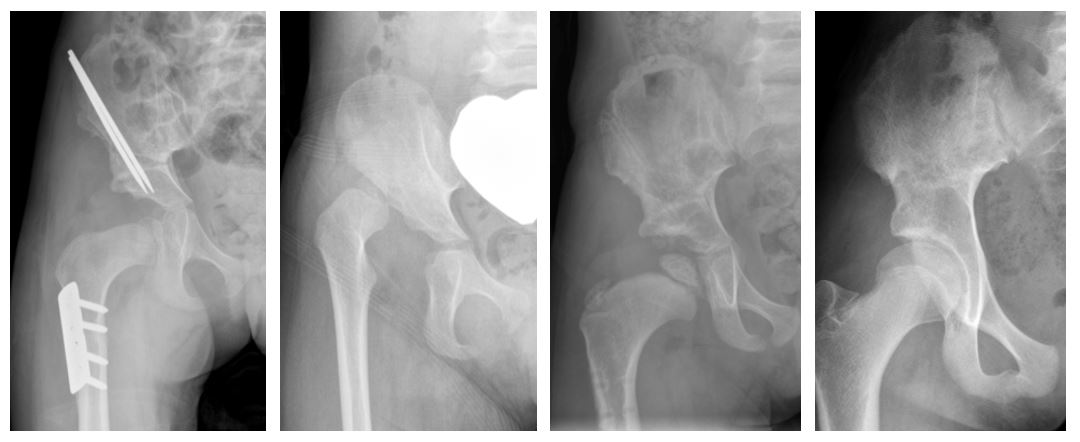

Periacetabular Osteotomy (PAO) is a complex procedure that corrects symptomatic developmental dysplasia of the hip (DDH). Intraoperative fluoroscopy allows for visualization of the entire pelvis and acetabulum, but its use exposes the patient and operating room staff to harmful radiation.

Surgical teams have primarily relied on standard fluoroscopy with an image intensifier (SFII), which converts X-rays into video images, to navigate the patient’s pelvic anatomy. In recent years, Children’s Hospital Colorado implemented flat panel detector (FPD) fluoroscope, a newer technology that offers more efficient image conversion to electronic data, higher resolution, fewer distortions and a smaller and more mobile design. For a number of pediatric procedures, FPD has reduced radiation exposure and improved navigational accuracy, but it has not been studied in hip preservation.

In this study, researchers in the Orthopedics Institute at Children’s Colorado compared SFII and FPD to identify the best method to minimize radiation exposure during PAO surgery. Fifty-three patients, mostly female, who underwent PAO between January 2019 and August 2020 were retrospectively reviewed and grouped by the type of fluoroscopy used. Study authors measured the total radiation exposure as well as the accuracy of lateral center edge angle images produced intraoperatively and at the six-week postoperative visit.

Compared to SFII, FPD reduced the total radiation dose by 78% and the radiation exposure time by 59%. Surgical time was also significantly reduced in the FPD group, which led to a significant decrease in the average radiation exposure time per surgical hour.

Additionally, when the accuracy of the images produced were compared, the mean difference between the lateral center edge angle measurements was minimal.

These findings suggest that FPD can reduce direct radiation exposure — including exposure time, dose and dose rate — during PAO, while maintaining a similar quality of surgical correction compared to the previous standard of care.